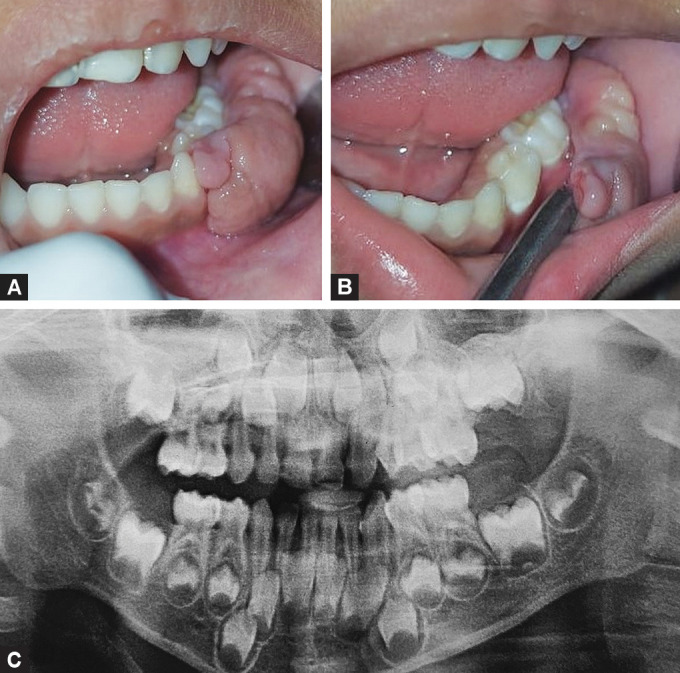

Aim and background: Congenital fibrous epulis (CFE) is an extremely rare benign gingival lesion of infancy that is typically observed in the maxillary alveolar crest, with its etiology still being unclear. Microscopically, it lacks the granular cells required for the standard diagnosis of congenital epulis (CE).

Case description: We report a case of CFE in a 4-year-old girl on the mandibular gingiva, which was interfering with the child's mastication and speech, for which excision was done under local anesthesia. The patient was followed up for a period of 1 year, and there was no evidence of recurrence.